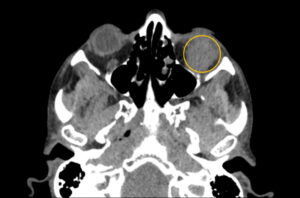

Inferior Rectus Abscess CT Axial Annotated. JETem 2025